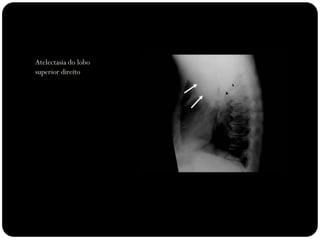

Atelectasia

 Diminuição de volume do segmento, deslocamento de uma ou mais

fissuras interlobares em direção à parte atelectasiada, desvio do mediastino

para o lado envolvido, deslocamento hilar, estreitamento dos espaços

intercostais e hiperinsuflação dos outros lobos / segmentos não atelectasiados

de forma compensatória.

Ex: Colapso do

LSD

Observar

deslocamento de

fissura!

Atelectasia do lobo

superior direito

Atelectasia do Lobo Sup. D.